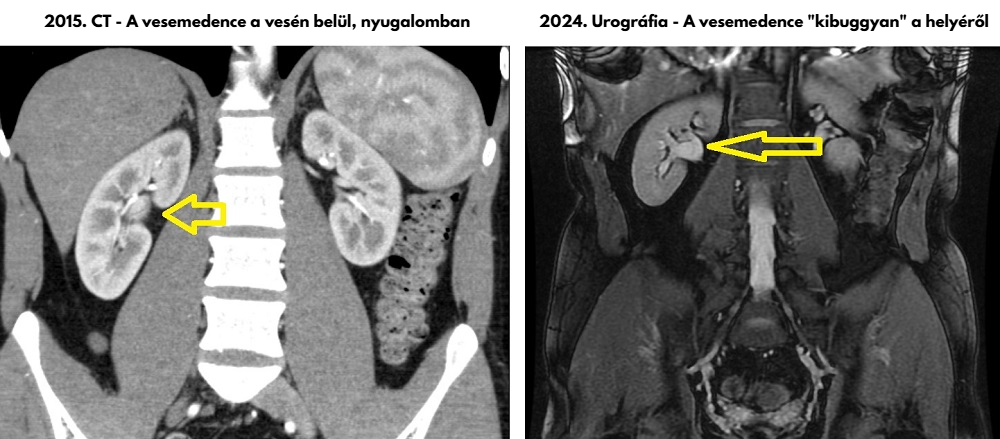

Súlyos kétoldali vesefájdalommal érkezett a fiam, aki túlélte a szeptikus állapotot, amivel itt volt először. Erre következetesen bal veséről írtak a felvételkor és a CT leletben. Merthogy történt egy CT Angiográfia. A vesemedencék (pyelonok) extrarenális helyzetűek – írta a távleletező viszonylag kezdő radiológus. A tatabányai kórházban ezt nem beszélték meg szakemberrel. Ami azért lett volna kulcsfontosságú, mert Zsoltnál azok nem veleszületetten voltak ilyenek, ahogy gondolták, hanem a fertőzés ideje alatt keletkeztek, akkor „csúsztak ki helyükről a vesén kívülről, nem is kicsit!” Ugyanezt igazolta az 1 hónappal korábbi MR urográfia is. Gyakorlatilag negatív leletet adtak ki, és a fiamat hazaküldték, miközben a veséi kiszakadtak a fájdalomtól és a neuropátiától (Cipro) úgy égett a teste, hogy az szavakkal nem fejezhető ki, elképesztő erő kellett, hogy kitartson. Mivel a fiamnak az addigra már 10 éve tartó betegsége alatt több tucat CT, CTA, MR, MRA és más képalkotó készült, pontosan visszanézhető milyenek voltak a veséi, milyen anatómiájúak, milyen vesékkel született – és hát nem extrarenális pyelonokkal. Teljesen normális anatómiájú, sosem fájó veséi voltak. Talán úgy mondanák szakmailag, intrarenalis pyelonjai voltak, a vesén belüli helyükön, ahogy kell. A vesén kívülre került vesemedencék a súlyos, közel 4 hónapja tartó kezeletlen vesemedence-gyulladás következményeként „csúsztak ki”. És lehet, hogy feszítik a magukkal „húzott” szöveteket, idegeket és ezért veszik meg a fiam a fájdalomtól!

Alább a 2024.05.21-én készült CTA egy képe a vesékről, vesemedencéről:

Érdemes megnézni az alábbi képet is – Hiába készítettük el Zsolt förtelmes kezeletlen állapotában is precízen, magánúton április 16-án az MR Urográfia vizsgálatot Veszprémben, az eredményeket már senki nem vetette össze, nem konzultálta meg, nem foglalkozott vele. Az alábbi képeket a fiam mentette ki a CT-ből és MR-ből. De ő azt mondja, a fenti kép szerinte jobban mutatja, milyen mértékben jött ki a helyéről a vesemedence!

Összefoglalva: a felvétel olyat mutat, amit korábban a kb húsz CT és MR felvétele soha. A vesemedencék kicsúsztak a veséből, extrarenálisak lettek a kezeletlen fertőzés miatt. Tehát nem veleszületetten „ampulláris tipusúak” – mint ahogy azt a veszprémi leletben írták (legyen mentségükre, hogy nem volt összehasonlító felvétel náluk). És lehet, hogy ez okozza az elviselhetetlen, kétoldali „kirepedő” érzést kiváltó vesefájdalmat? A háziorvos szerint, aki korábban sebész volt, lehet, hogy a korábban gyulladt, megduzzadt vesemedencék kicsúszva a veséből húzzák a vesetokot? Ezt kellene radiológusnak, urológusnak együtt kivizsgálni, hogy végre kiderüljön az embertelen vesefájdalom oka. Lehet, hogy ez eljuttathat a megoldáshoz, a fiam szenvedésének megszűnéséhez.